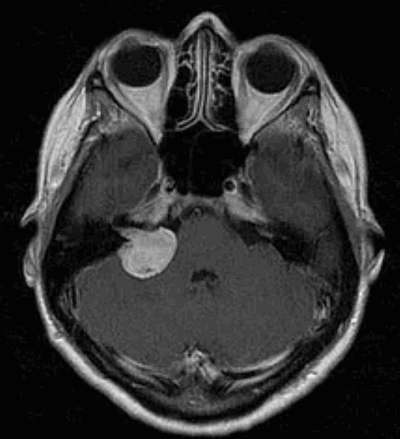

Наиболее информативным методом выявления вестибулярных шванном является МРТ головного мозга с контрастным усилением в режиме Т1 и Т2. Это исследование позволяет определить размеры опухоли, наличие перитуморозного отека, наличие признаков окклюзионной гидроцефалии, которая может быть следствием сдавления опухолью IV желудочка. Кроме этого МРТ позволяет провести дифференциальную диагностику с другими опухолями схожей локализации (чаще с менингиомой задней грани пирамиды височной кости). Еще одним стандартом диагностики является КТ в костном режиме. Независимо от снижения слуха стандартом является проведение аппаратной аудиографии.

Вестибулярная шваннома (невринома VIII нерва, акустическая невринома) представляет собой доброкачественное новообразование, возникающее из шванновских клеток вестибулярной порции VIII нерва.